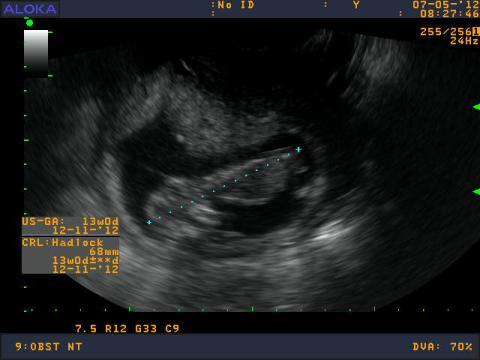

Pro větší náhled klikněte na obrázek

Dobrý deň,chcela by som sa opytat. Gynekolog mi robil v 13tt vaginalne UTZ - meranie myslim ze sa vola CRL, lekar mi povedal, ze mam zle tkanivo na sonograf, že aby som sa neplašila, niektoré ženy ho maju dobre a niektoré zle, že to nemá vplyv na vyvoj dieťatka ale že malého nieje dobre vidno aj obrazok zo sona je nejasnejší oproti iným bábätkam v gestačnom tyždni 13tt, čiže meranie NT neprebehlo tak ako malo. Do materskej knižky mi napísal nepriaznivá poloha...prítomnosť nosoej kostičky tiež neviem. Vďaka tomu tkanivu, ale pri ukončení sona ma ubezpečil, že je to vitálna gravidita. Videla som špunta ako si tam v brušku robi kotrmelce a kopká. Ako mu bije srdiečko. Je pravda, že ked som bola 3 tyždne dozadu na UTZ srdiečko som lepšie videla ako teraz, dokonca vtedy som jasnejsie videla ručičky a nožičky. Musela som až oči prižmuriť. Možem to tkanivo nejako ovplyvniť? alebo jeto od prírody dané? a ešte otazočka. Mám sa znepokojovať ked nemám vobec to meranie NT vdaka tkanivu? este som zabudla babatko ma 68mm. Dakujem za odpoved. :-)

Dobrý den. S vlastnostmi vaší táně se nedá nic dělat. NT by ale zkušený gynekolog měl být schopen změřit vždycky (pokud to nejde přes břicho, měl by použít vaginální sondu).